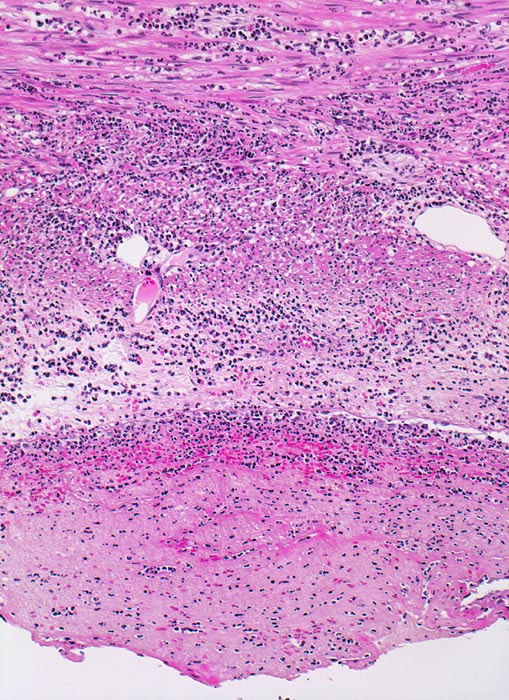

Das histologische Kriterium für eine akute Appendizitis ist die Infiltration der Muscularis propria mit neutrophilen Granulozyten.

• Diffuse Durchsetzung der Appendixwand mit neutrophilen Granulozyten (phlegmonöse Entzündung).

• Fibrinauflagerungen auf der Serosa durchmischt mit neutrophilen Granulozyten (fibrinös eitrige Peritonitis). Das sollte der Kliniker dem Pathologen mitteilen: